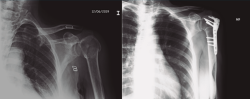

Protocolo rehabilitador tras la implantación de prótesis invertida total de hombro (Tabla 2 y Figura 9)

Figura 9. Radiografía de una fractura de húmero pre- y posprótesis invertida.